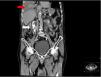

A thoracentesis was performed obtaining a yellowish pleural fluid. Its analysis showed a mononuclear exudate: glucose 149mg/dL; total protein 3.6g/dL; albumin 2.5g/dL; LDH 286IU/L, pH 7.35; pleural fluid/serum protein ratio 0.6; pleural fluid/serum LDH ratio 1.56. A 1500ml chest drain was also performed improving the symptoms, although only partially. CT revealed a still large right pleural effusion with no evidence of underlying pulmonary or diaphragmatic pathology. Likewise, a bladder balloon and a rupture of both ureters with contrast extravasation and formation of urinomas bilaterally, greater on the right, were evidenced, with discreet hyper-uptake of both ureters in relation to urethritis, as well as a notable increase in prostate size (Fig. 1).